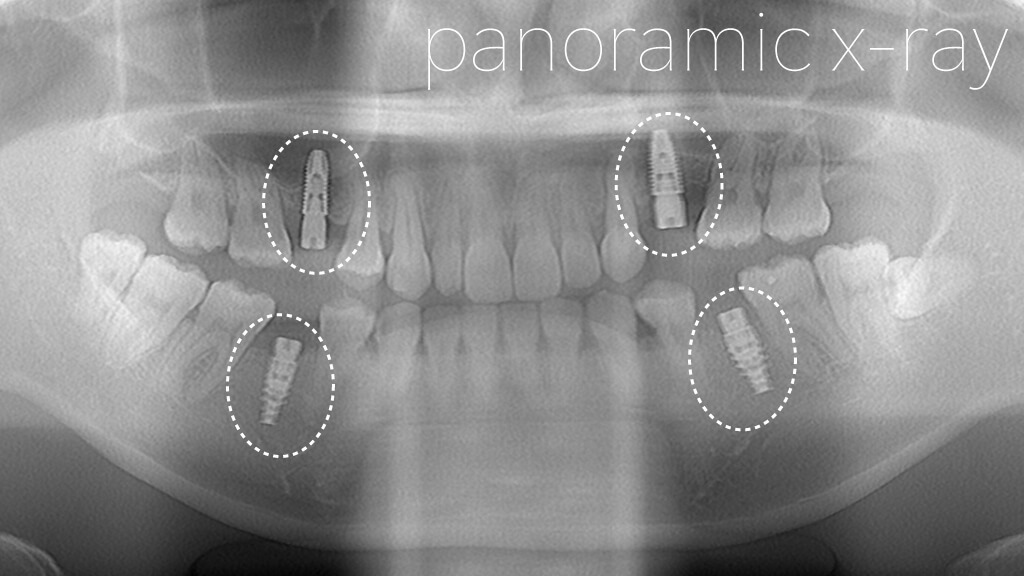

8.術後オルソ

今回は、上下左右それぞれ1本ずつ、合計4本のインプラントを埋入しています。

上顎については、左右ともに上顎洞(サイナス)までの骨の高さが不足していたため、「Densah® Bur(デンサーバー)」を用いたサイナスリフトを併用しました。

上顎の奥歯の部分は、歯を失った後に骨が吸収されやすく、インプラントを埋入するために必要な骨の高さ(垂直的な骨量)が不足していることがよくあります。

このような場合には、上顎洞(サイナス)という空洞の底を持ち上げて骨を増やす処置である「サイナスリフト」を行い、インプラントを安全に埋入できる骨の高さを確保します。

今回は、Densah® Bur(デンサーバー)という特殊なドリルを使用し、骨を削るのではなく押し広げるように形成することで、骨を温存しながらサイナスリフトを行いました。

これにより、骨への負担を抑えながら、インプラントの初期固定をしっかり確保した状態で埋入することができました。